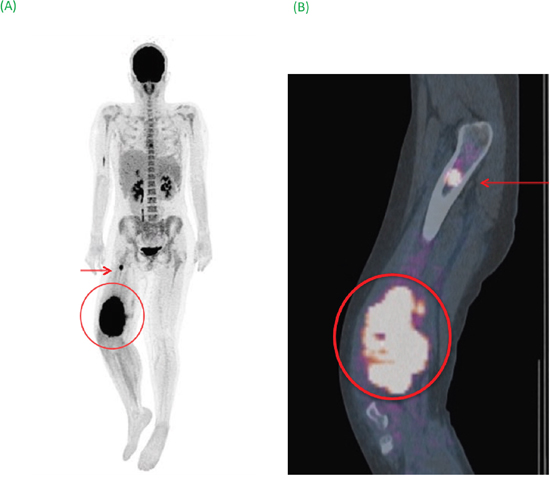

Figure 2: (A) Maximum image projection (MIP) showed the primary tumor surrounded associated with bone metastatic site (arrow). (B) Sagittal fusion FDG-PET/CT image specified lesions’ anatomical locations. Semi-quantitative PET parameters of the primary tumor (SUVmax of 29 and SUVpeak of 20.57) were associated with a poor prognosis (OS: 9 months).